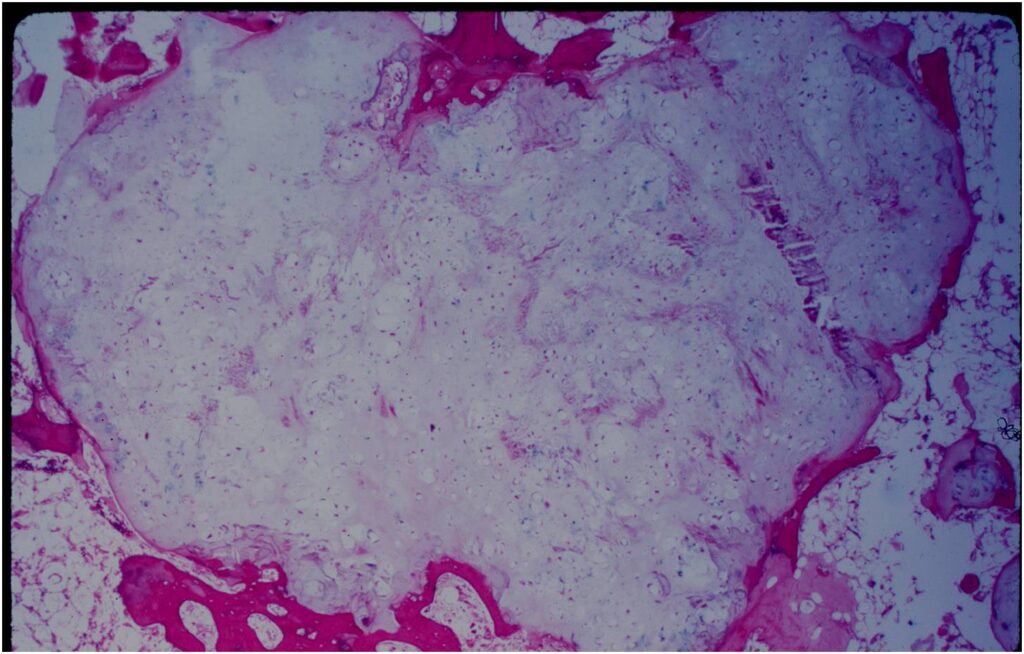

Pathology

- Rests of hyaline cartilage with a lobular growth pattern

- Cells are within lacunae

- Hypocellular with cells spaced apart separated by matrix

- Cells have small nuclei and are similar size and shape (no pleomorphism)

- No mitotic figures

- The matrix has a ground glass basophilic appearance

- The matrix contains glycosaminoglycans that attract fluid/water and gives it a bsophilic appearance and show as high signal intensity on T2 weighted MRI

- The collagen of the matrix is organized in a manner such that the refractile index under a microscope gives a ground glass appearance to the matrix. One can not visualize the actual collagen fibers.

Microscopic Pathology

- Enchondromas are well defined lesions with cartilage arranged in lobules that are separated by fibrovascular septa

- Enchondral ossification may occur around periphery of lobules and when calcified appear as “Rings and Arcs” on X-rays

- Cells are in lacunae and have small dark nuclei

- Low cell count, cells appear bland with few chondrocytes and are similar size and shape

- Although some enchondromas may have areas that are hypercellular and may have two or three cells within a lacunae

- No entrapment or destruction of trabeculae

- There should be no myxoid change in long bone lesions (there is occasional myxoid change in enchondromas of the digits)